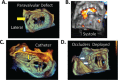

Echocardiography has evolved over the past 45 years from a simple M-mode tracing to an array of technologies that include two-dimensional imaging, pulsed and continuous wave spectral Doppler, color flow and tissue Doppler, and transesophageal echocardiography. Together, these modalities provide a comprehensive anatomic and functional evaluation of cardiac chambers and valves, pericardium, and ascending and descending aorta. The switch from analog to digital signal processing revolutionized the field of ultrasound, resulting in improved image resolution, smaller instrumentation that allows bedside evaluation and diagnosis of patients, and digital image storage for more accurate quantification and comparison with previous studies. It also opened the door for new advances such as harmonic imaging, automated border detection and quantification, 3-dimensional imaging, and speckle tracking. This article offers an overview of some newer developments in echocardiography and their promising applications.